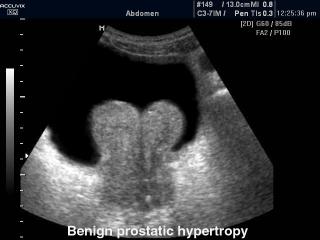

В разделе "Урология" атласа представлены результаты ультразвуковых исследований мужских заболеваний. Здесь вы можете посмотреть эхограммы мочевого пузыря, предстательной железы и др. Эхографию почек см. в "Абдоминальные исследования".

В разделе "Эхография в урологии" журнала "SonoAce-Ultrasound" Вы можете ознакомиться с публикациями врачей по теме.